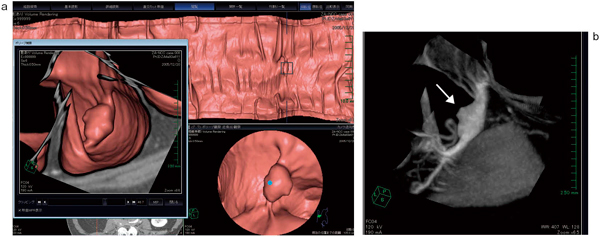

VirtualPlace雷神では,“ポリープ観察機能”により診断対象物の任意断面の拡大MPRを表示し,詳細な読影が可能である。また,今回新しく“キューブビュー”が搭載され(図3),選択した観察部位の周辺部分を限定的に表示し,歪みのない3D volume rendering表示による詳細な形状観察が可能となっている。また,その限定領域内においてMIP表示が可能となっており,経静脈性造影剤を使用した場合は造影効果を,fecal tagging を行った際にはtaggingの効果も表示できる。このMIP表示は展開像においても利用可能となっており,今後さまざまな活用が期待できる表示法といえるだろう(図4)。

図3 キューブビュー(cube view)

a:図2と同一症例。仮想内視鏡画像,展開像,キューブビューそれぞれでの描出のされ方の違いが興味深い。キューブビュー上では歪みのない表示が達成されている。

b:同病変のMIP画像。経静脈性造影剤投与後であり,腫瘍相当位置(→)の造影効果が反映されたMIP画像となっている。

図4 展開像におけるMIP表示

a:図2と同一症例。

b:MIP表示。カラーリングを調整することで,腫瘍が色づいて見える。